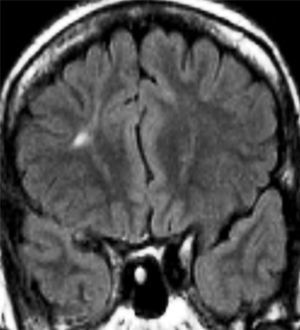

Los hallazgos en las IRM se pueden observar en las figuras 1–8. Se observa predominancia en el diagnóstico de esclerosis del hipocampo en los pacientes con epilepsia temporal, tanto en el grupo de enfermos respondedores como no respondedores. En la epilepsia extratemporal se observa con mayor frecuencia la presencia de malformaciones del desarrollo cortical y/o tumores, que fueron consideradas en el mismo grupo debido a que estas lesiones muchas veces resultan indistinguibles unas de otras a través de las IRM. Esta predominancia se observa más acentuada en el grupo de enfermos resistentes al tratamiento.